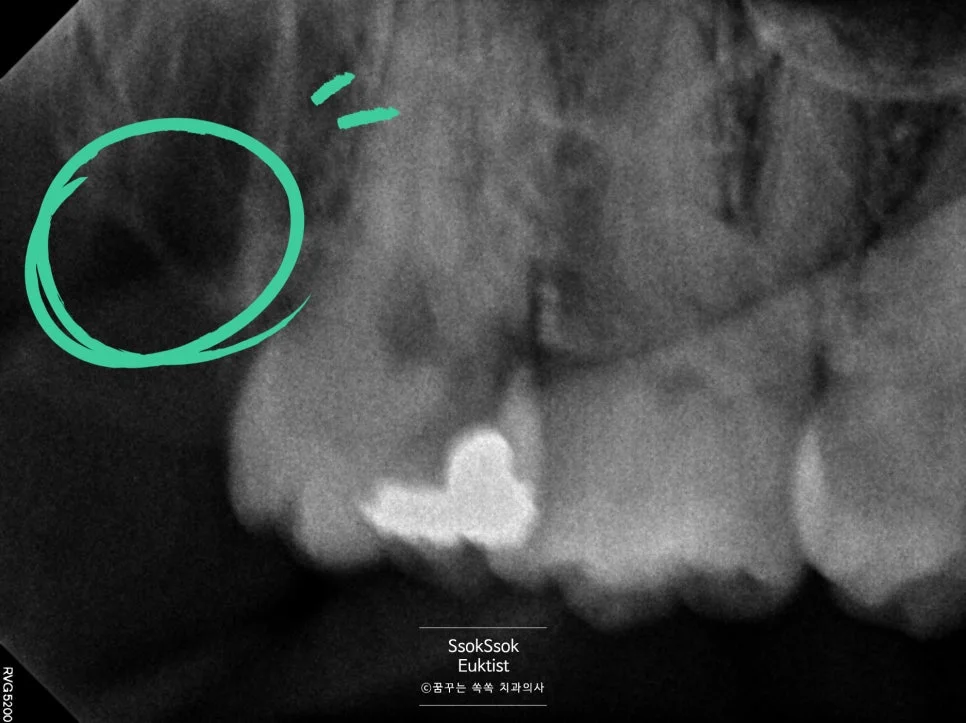

오른쪽 아래 사랑니의 경우 신경관과 바로 붙어 있습니다.

오른쪽 아래 사랑니 — 신경관과 바로 붙어 있는 상태

하지만 그보다 더 걱정인 건 사랑니 뿌리의 모양인데요.

사랑니 뿌리가 서로 다른 방향으로 휘어 있는 구조

뿌리가 서로 다른 방향으로 휘어 있어 한 번에 나올 수 없는 상황인데요. 이런 경우 뿌리가 전부 나오지 않고 뿌리의 조각이 일부 남아 있게 될 수 있습니다.